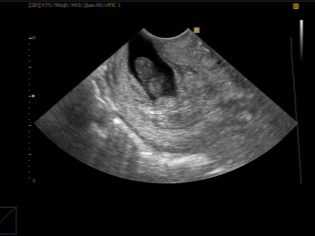

- По данным ультразвукового исследования:

на календаре отметить дату ультразвукового исследования. Сроку беременности, определенному на УЗИ, добавить оставшиеся недели до 40 - получить дату предполагаемого срока родов.

Обычно в этом случае на раннем сроке проводится УЗИ, которые позволяет установить ПДР в зависимости от текущего срока по размерам плодного яйца и КТР — копчико-теменному размеру плода.

Ультразвуковое исследование для установления срока беременности и ПДР наиболее эффективно только на ранних сроках — до 10-12 недель беременности. Потом появляется большая погрешность. Дело в том, что эмбрионы растут приблизительно с одинаковой скоростью, и пока идут процессы эмбриогенеза, развитие всех малышей протекает почти одинаково.

- по данным ультразвукового исследования. Точность определения срока беременности по данным ультразвукового исследования достаточно высока, особенно в первом триместре беременности. Во 2 и 3 триместрах ошибка определения срока беременности этим методом повышается, что связано с конституциональными особенностями развития плода или осложнениями беременности (гипотрофия плода, диабетическая фетопатия и т.д), поэтому определенную ценность представляет динамическое ультразвуковое наблюдение за плодом.